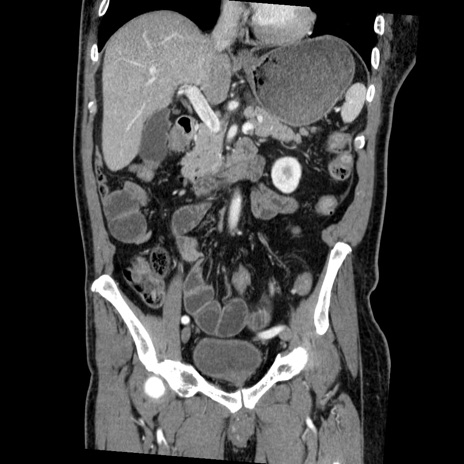

症例22(冠状断像)

【症例】50歳代男性

【主訴】腹痛

【現病歴】AVMからの被殻出血のため回復期リハ病棟入院中。 本日午後3時頃急に下腹部痛が出現した。

【既往歴】AVM、被殻出血、虫垂炎、高血圧

【身体所見】意識晴明、左半身不全麻痺、会話の理解は良好、36.5°C、腹部:膨隆、全体に板状硬、下腹部正中に圧痛点あり、反跳痛-、筋性防御不明、右下腹部にope scar

【データ】WBC 9400、CRP 0.06